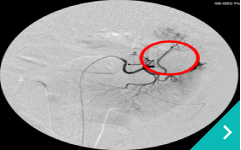

IVRとは、レントゲン透視(X線)や超音波などの画像を使いながら、カテーテルという細い管を体内に通して、病気のある部位を治療する方法です。開胸や開腹をせずに治療できることから、体への負担が少なく、多くのわんちゃん・ねこちゃんにとって優しい選択肢となります。

門脈シャントコイル塞栓術

門脈シャント

コイル塞栓術

肝臓腫瘤に対する肝動脈塞栓術

肝臓腫瘤に対する

肝動脈塞栓術